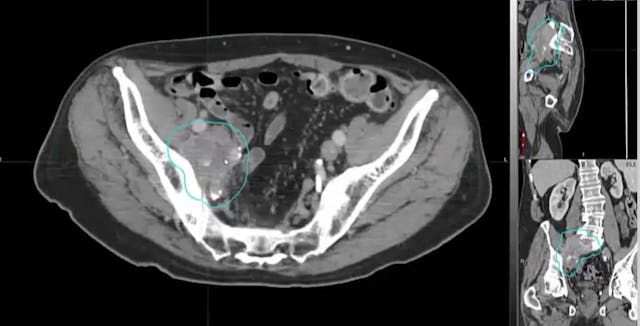

03/24/2022 - Dr. Ronald Chen - Radiation Oncology - GU

Chartrounds US - GU